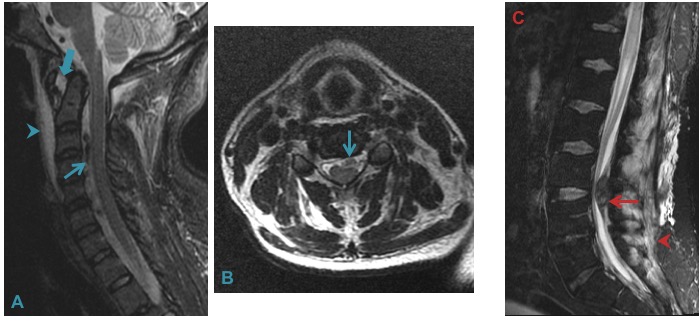

Post traumatic epidural hemorrhage (A & B) with C1-2 subluxation (solid arrow) and prevertebral edema (arrowhead). Post lumbar puncture hemorrhage (picture on extreme left) in the setting of acute leukemia and thrombocytopenia. Incidental paraspinal edema.

Relative T1 hyperintensity (A), hemosiderin rim (B) and hyperdensity on CT (C) aided in the diagnosis of epidural hemorrhage in this young patient. The cause of hemorrhage albeit, remained elusive after extensive work up.